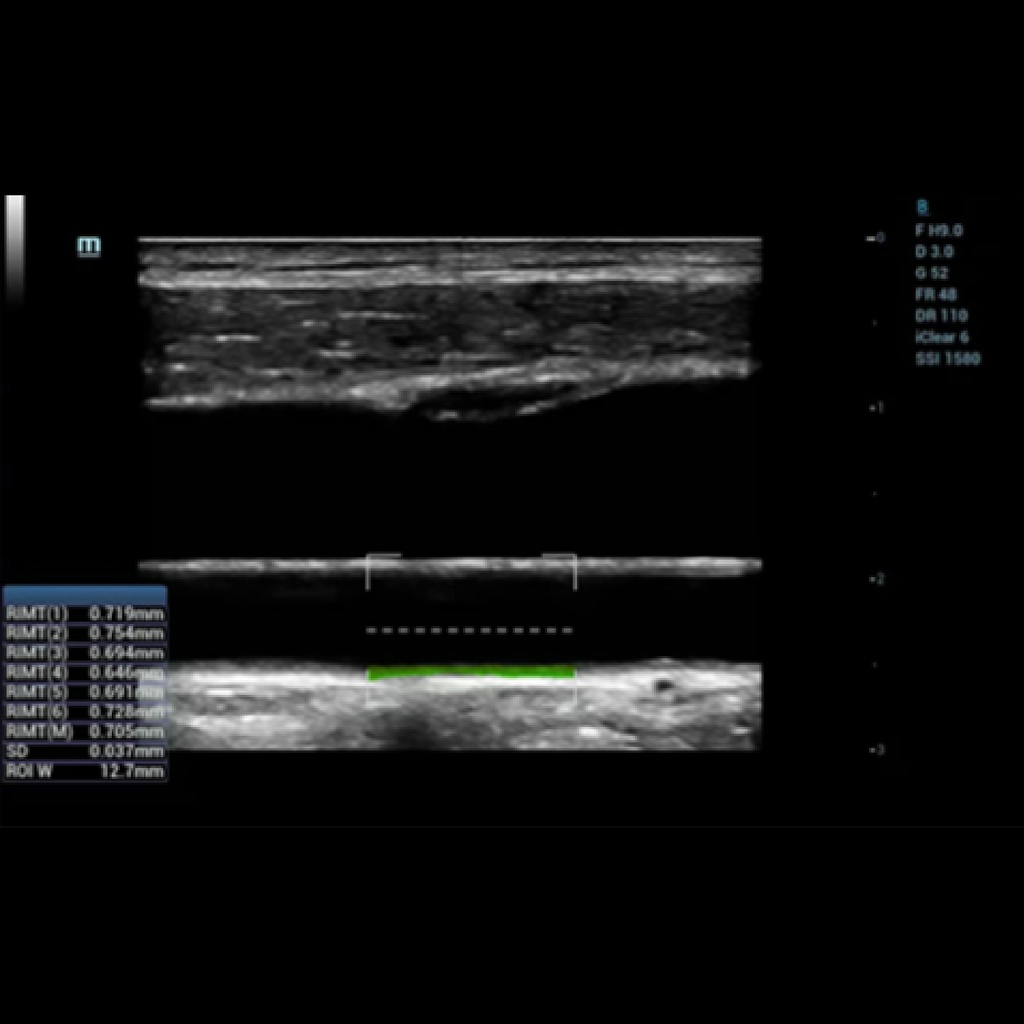

Медицински метод за откриване на сърдечно-съдови заболявания. RIMT: дебелината на интимално-медиалния слой (IMT), че е важен показател за оценка на състоянието на пациента за риска от бъдещи сърдечносъдови инциденти.